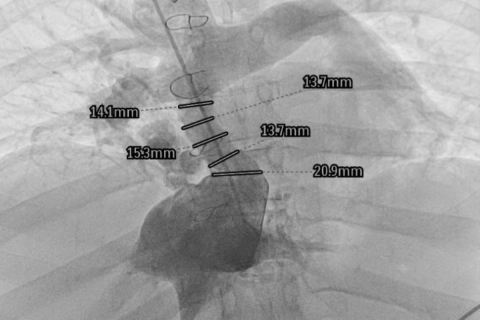

In this female patient, the surgically implanted conduit that brings blood from the inferior vena cava to the pulmonary vascular bed had narrowed down significantly. Using access through the superior vena cava (both femoral veins were obstructed), the cardiologists performing the intervention broadened the conduit with a stent graft, with a very good effect.